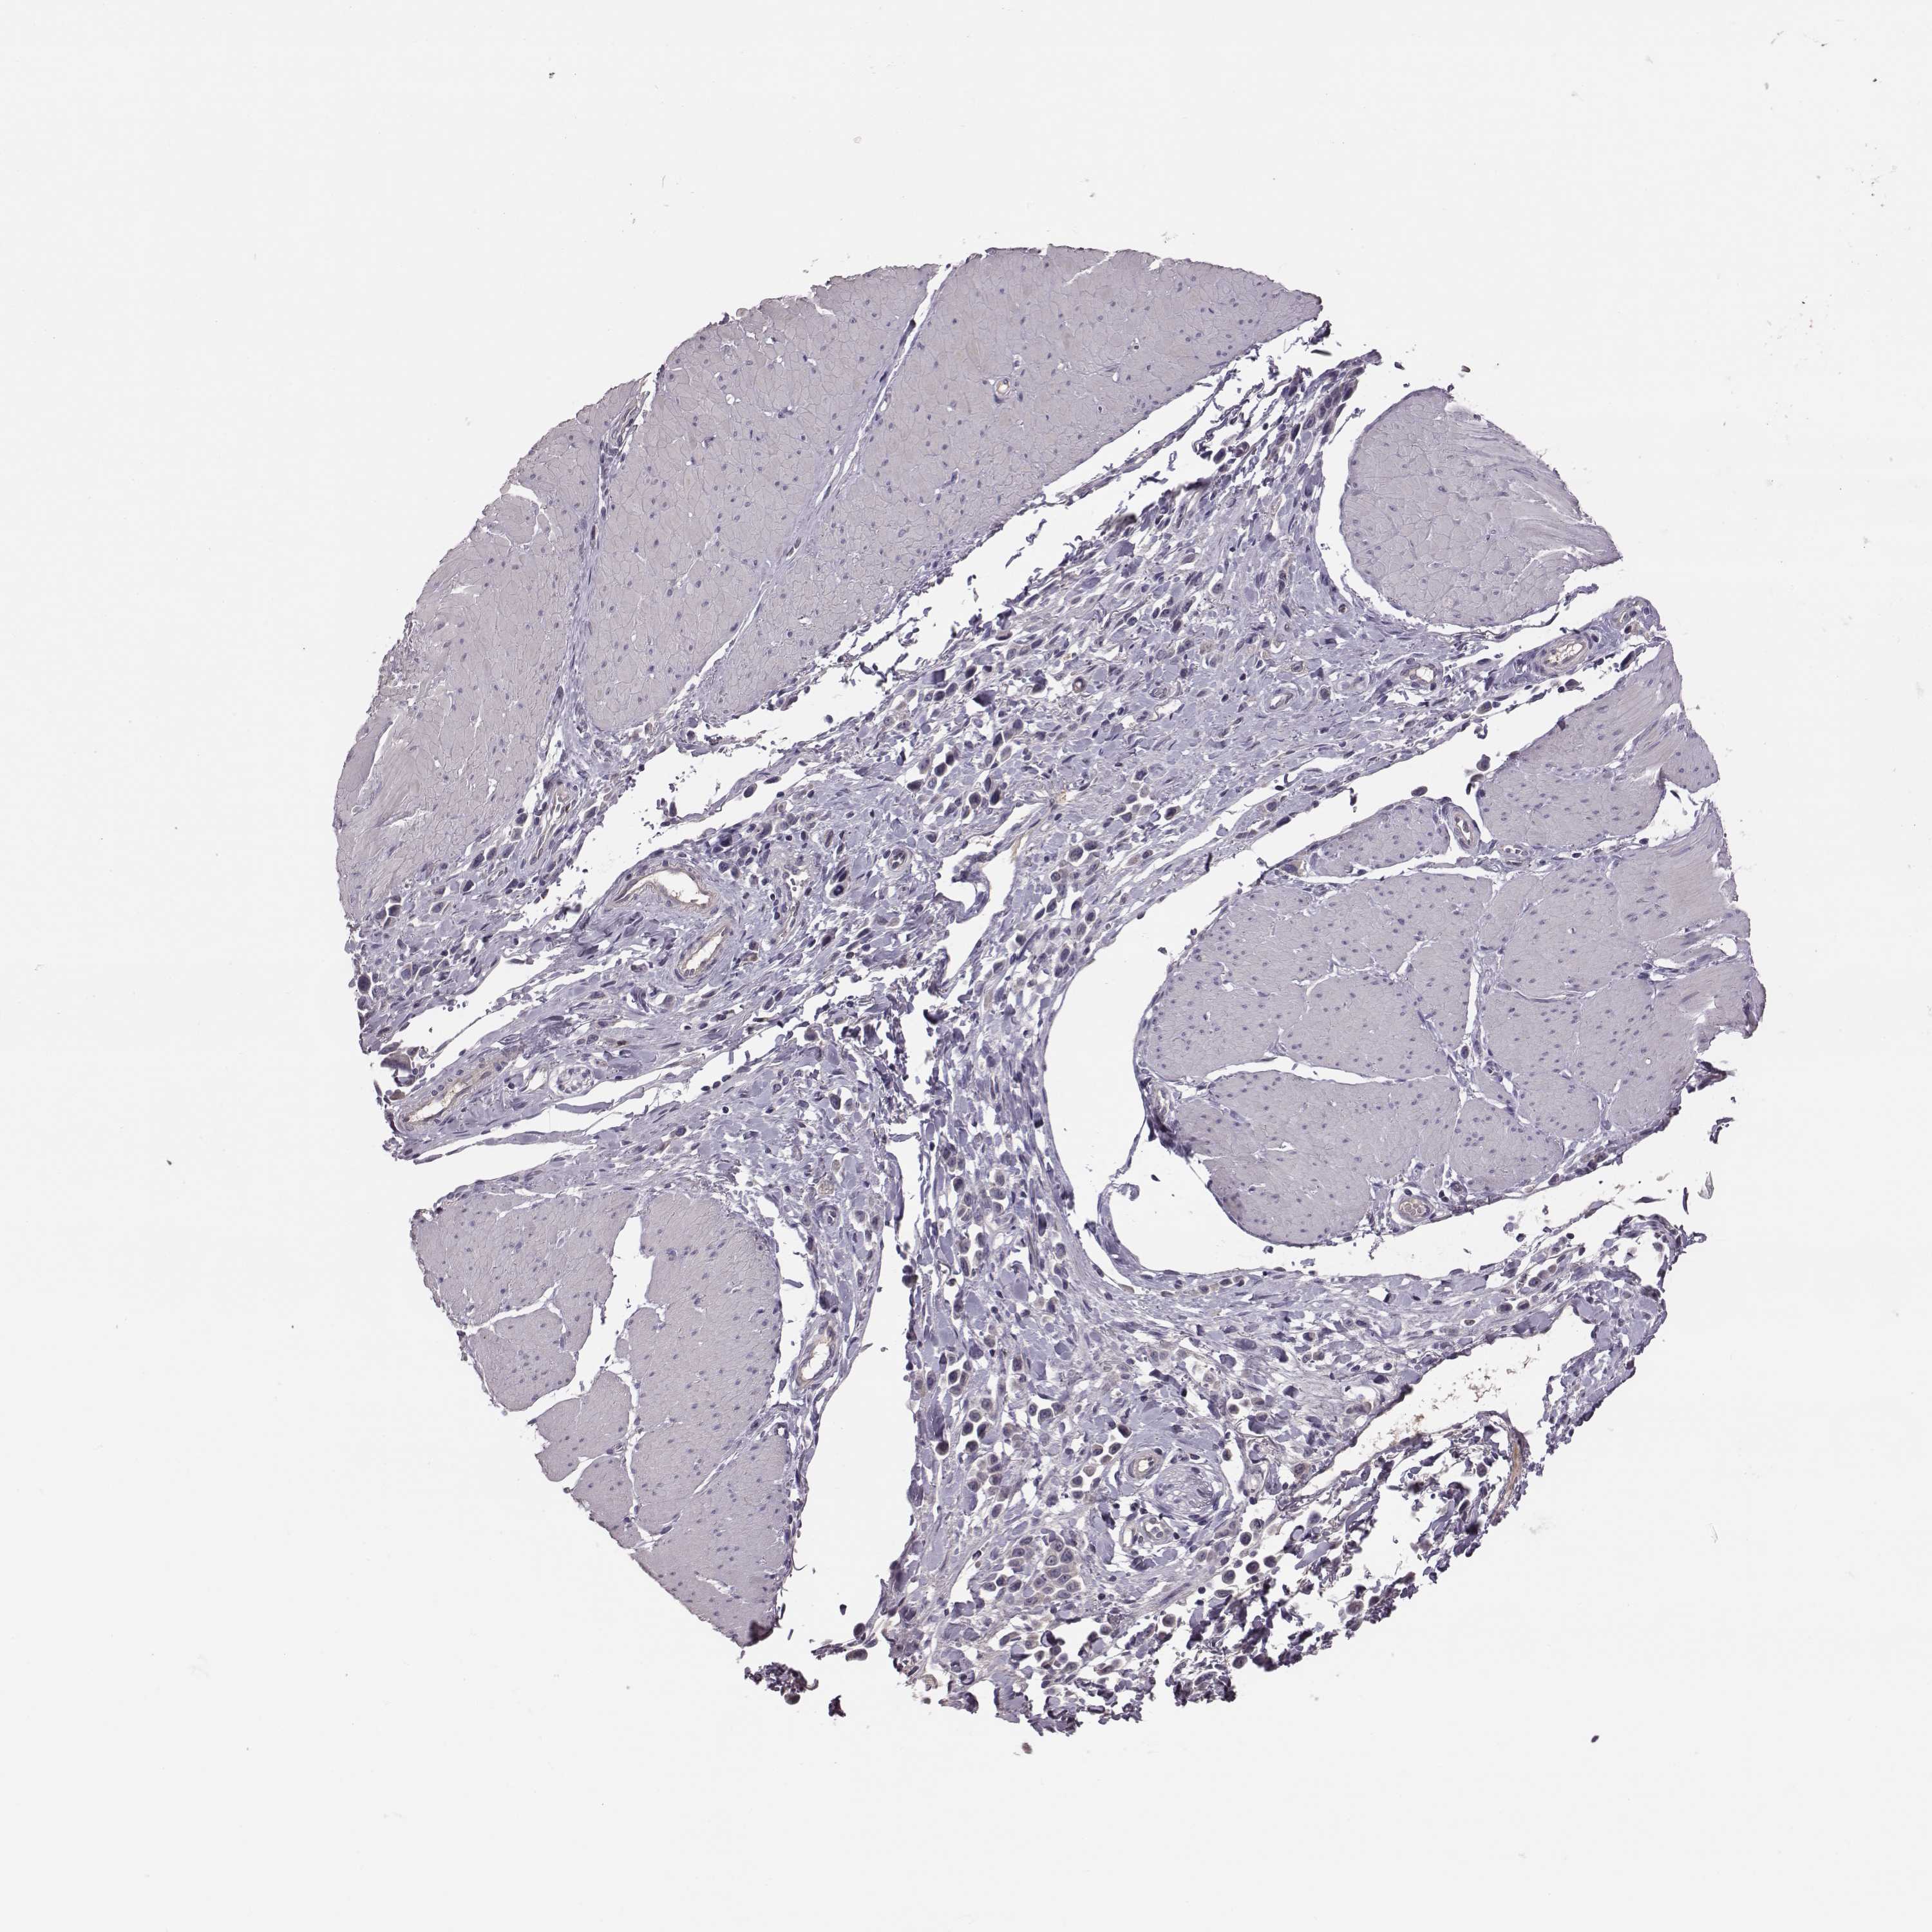

STOMACH CANCER - Protein expressioni

A mouse-over function shows sample information and annotation data. Click on an image to view it in a full screen mode. Samples can be filtered based on level of antibody staining by selecting one or several of the following categories: high, medium, low and not detected. The assay and annotation is described here.

Antibody stainingi

Antibody staining in the annotated cell types in the current human tissue is reported as not detected, low, medium, or high, based on conventional immunohistochemistry profiling in selected tissues. This score is based on the combination of the staining intensity and fraction of stained cells.

Each image is clickable and will lead to virtual microscopy that enables deeper exploration of all samples and also displays staining intensity scores, fraction scores and subcellular localization as well as patient and tissue information for each sample.

Adenocarcinoma, NOS